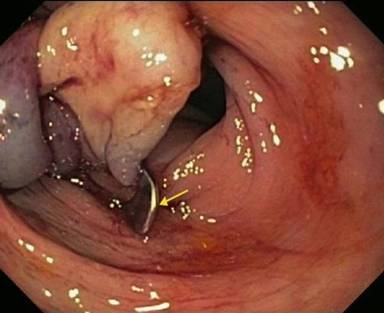

Because pancreatic sphincterotomy and pancreatic duct stenting was unsuccessful, we attempted endoscopic clip closure of the fistula. A 0.025” angled guidewire was advanced into the pancreatic duct, across the fistula, and into the colon. The duodenoscope was removed, leaving the wire in place. An over-the-scope clip (Ovesco, Campbell, CA, USA) was attached to the end of a colonoscope which was advanced to the splenic flexure (Figure 2). The fistula was identified by the wire protruding from it (Figure 3). The cap was positioned en face to the fistula and the wire slowly withdrawn. Using a grasper, tissue was pulled into the cap and suction applied. The clip was deployed and in good position (Figure 4).

Figure 4. An endoscopic view of the deployed over-the-scope clip and closure of the fistula from the colonic side (arrow). |